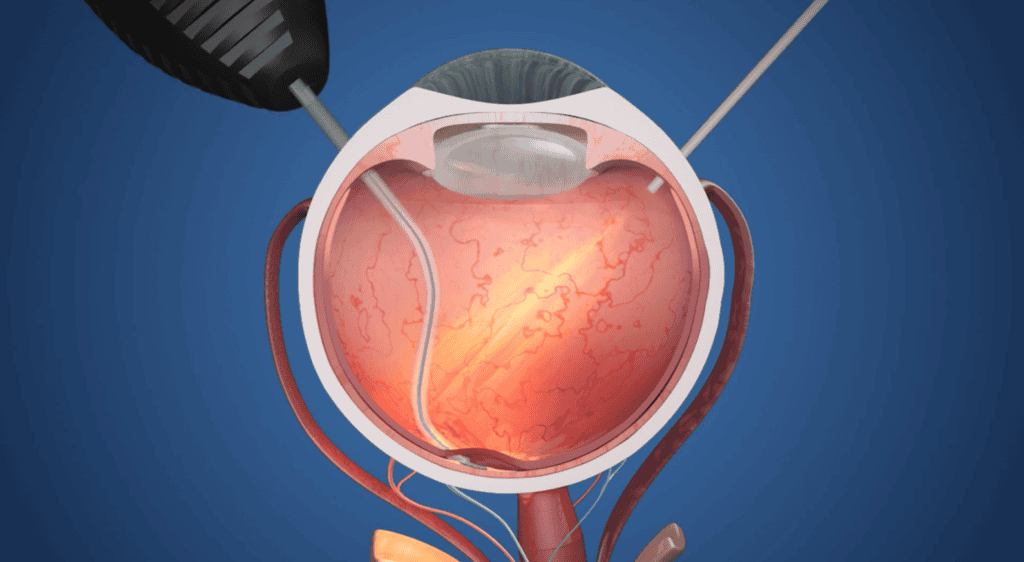

ชิป Prima ประกอบด้วยชิปสี่เหลี่ยมจัตุรัสขนาด 2 มม. ที่ถูกผ่าตัดวางไว้ใต้จอประสาทตา ตรงส่วนหลังสุดของลูกตา โดยใช้เวลาผ่าตัดนานถึง 80 นาที โดยจะใช้งานร่วมกับแว่นตาพร้อมกับกล้องที่จะบันทึกภาพ และส่งแสงอินฟราเรดไปยังชิป แล้วชิปดังกล่าวจะทำหน้าที่เสมือนแผงโซลาร์เซลล์ขนาดเล็ก ที่จะแปลงแสงเป็นการกระตุ้นไฟฟ้า และส่งไปยังสมอง จากนั้นสมองจะตีความสัญญาณดังกล่าวเป็นภาพ ซึ่งเป็นการเลียนแบบกระบวนการการมองเห็นตามธรรมชาติ

ในโรคจอประสาทตาเสื่อมตามวัย เซลล์เฉพาะทางที่เรียกว่าโฟโตรีเซพเตอร์เซลล์ (Photoreceptor cell) จะได้รับความเสียหายเมื่อเวลาผ่านไป โฟโตรีเซพเตอร์เซลล์ซึ่งอยู่บริเวณด้านหลังของจอประสาทตาจะแปลงแสงให้เป็นสัญญาณที่ส่งไปยังสมอง “ถึงแม้ว่าโฟโตรีเซพเตอร์จะใช้การไม่ได้ แต่จอประสาทตาจะยังคงอยู่เป็นส่วนใหญ่ ในแนวทางของเรา อิมแพลนต์จะเข้ามาแทนที่โฟโตรีเซพเตอร์” Daniel Palanker, ศาสตราจารย์ด้านจักษุวิทยาที่มหาวิทยาลัยสแตนฟอร์ด ผู้ประดิษฐ์อิมแพลนต์ Prima กล่าว